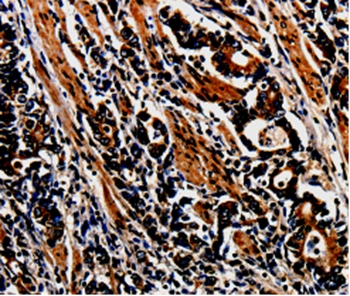

Immunohistochemical analysis of paraffin-embedded Human tonsil cancer tissue using #35550 at dilution 1/10.

Immunohistochemical analysis of paraffin-embedded Human stomach cancer tissue using #35550 at dilution 1/10.